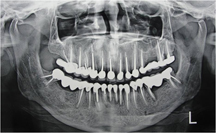

This phase was completed in one week and consisted of restoring maxillary and mandibular anteriors with custom made post and core [Table/Fig-3] and definite restorations. Full veneer PFM crowns were done in 2-2 units of teeth # 12 &13, 22 &23, 32 &33, 31 &41 and 42 &43. #11 and #21 were individually given separate PFM crowns. Final cementation was done with Type I Glass ionomer cement after reviewing for position, shape, and shade of crowns.

In the next appointment any residual bonding material was removed and final adjustments were made. End-treatment photographs [Table/Fig-4a,b,c] and O.P.G [Table/Fig-5] was taken.

Post-operative orthopantomogram